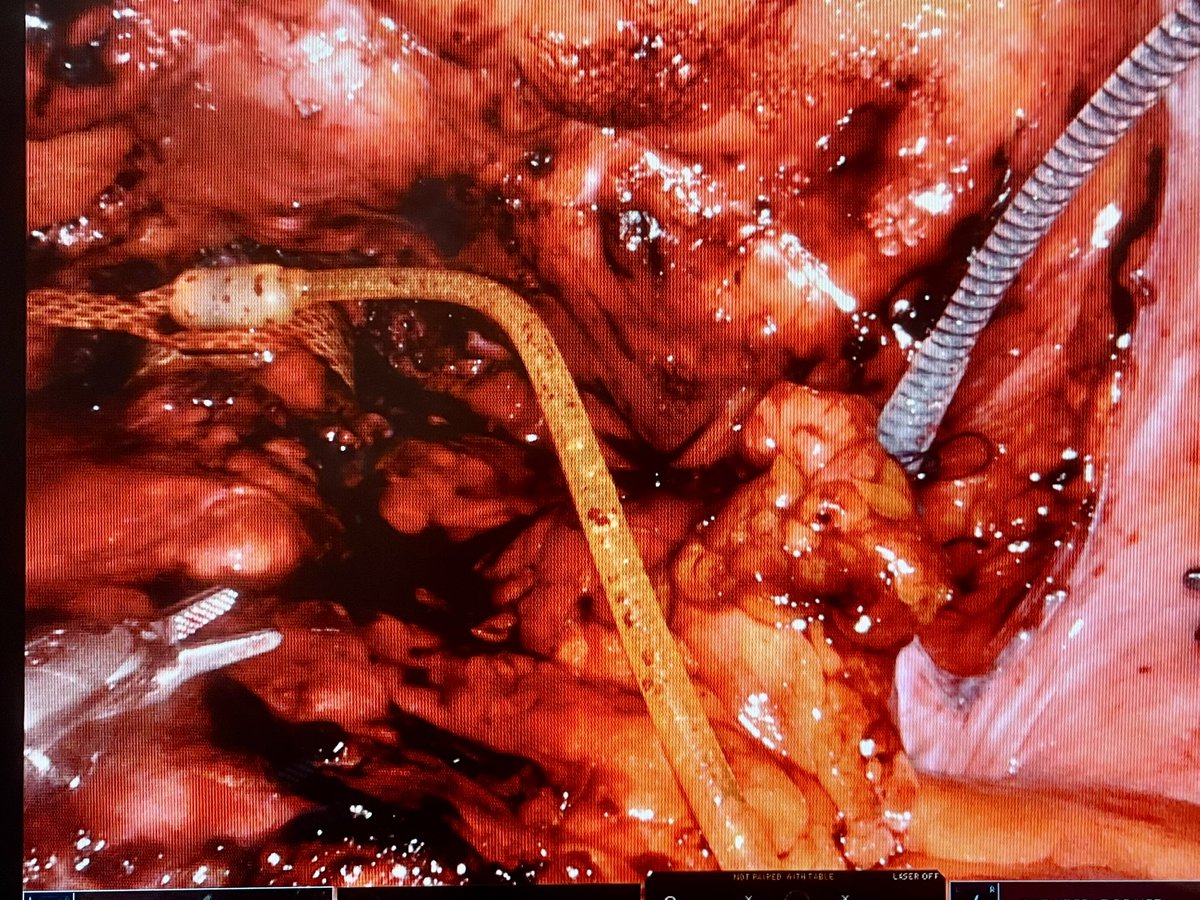

🙏 to my team Macquarie University Hosp. 6/12 ago today another robotic female #AMS800 implanted. Now pt QoL much improved. Suitable in ISD refrac to failed slings, ISD with det underactivity. Society of Robotic Surgery | SRS SUFU ICS A Woman's Urologist

Gradually accruing experience in robotic female BN #AMS800 sphincter. Now I isolate the resovoir in a separate pocket using subperitoneal fat in the obturator fossa to avoid it moving around in the pelvis. Works well in last several cases. USANZ Benoît Peyronnet Boston Scientific Urology